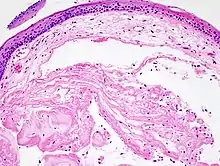

Um nódulo, em patologia, é uma lesão sólida, elevada, com mais de 1 cm de diâmetro. É geralmente bem delimitado e de origem epitelial ou conjuntiva.

Pode ser pediculada ou séssil. Quando não está se expandindo, é classificado como benigno e, quando está é classificado como maligno. Suas características variam muito dependendo do lugar que se localiza (pulmão, mama, axila, tireoide e cordas vocais).